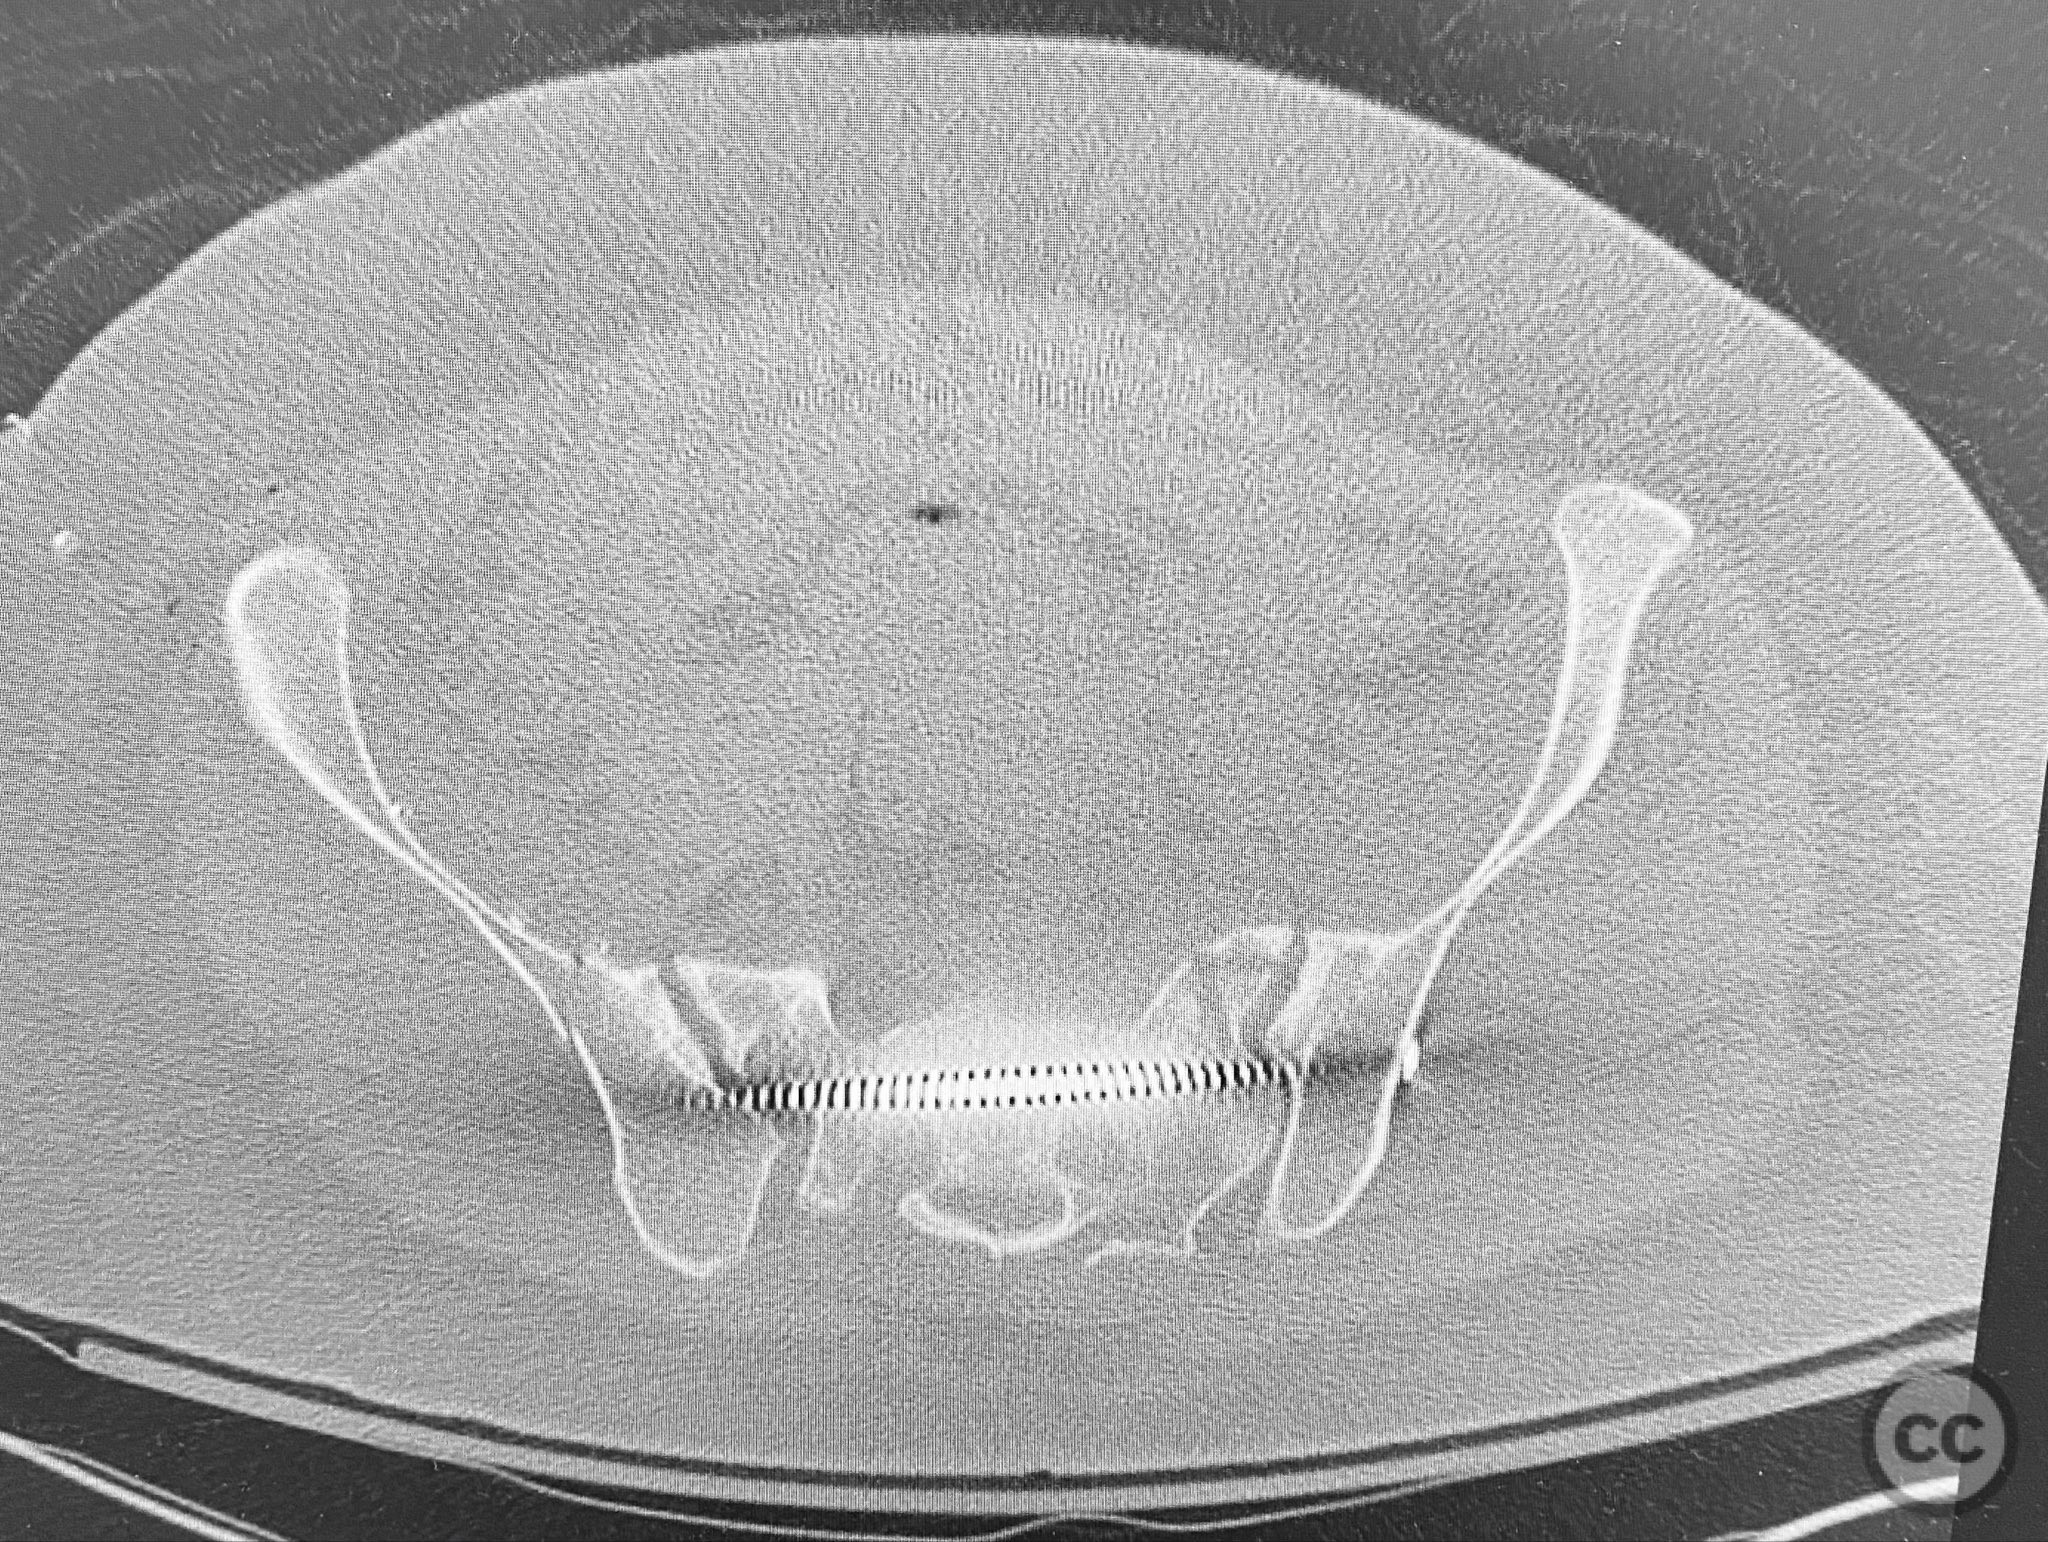

Clinical and radiological findings:  The patient presented following trauma with an unusual, significantly displaced right iliac fracture, accompanied by left-sided sacral and parasymphyseal ramus fractures. Initial AP pelvic radiography demonstrated the complex injury pattern. CT imaging provided detailed characterization of the iliac and sacral fractures, including assessment of displacement, bone quality, soft tissue status, and overall body habitus. No neurovascular compromise was reported. AO/OTA classification: Right iliac fracture 61B2.3 (partial unstable, lateral compression injury), left sacral fracture Denis zone I, left parasymphyseal ramus fracture.

Bilateral distal femoral traction resulted in excellent reduction of the sacral fracture but did not adequately reduce the iliac displacement. Percutaneous fixation of the sacrum was performed first, followed by open reduction of the iliac fracture. Intraoperative imaging confirmed that all implants were fully contained within the available osseous corridors, avoiding extraosseous penetration. The complexity of the iliac fracture required careful anatomical reduction and implant placement along the pelvic brim.

Orthopaedic implants used:   Pelvic brim contoured plate, cancellous screws, percutaneous sacral screw(s)